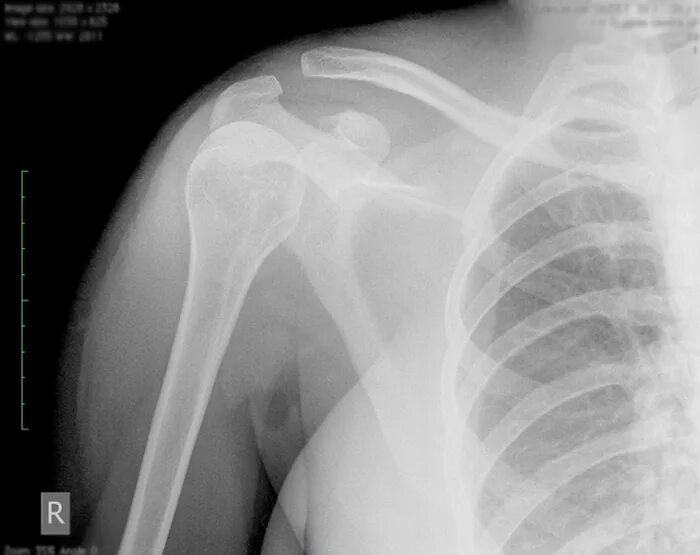

Вывих акромиально ключичного сочленения